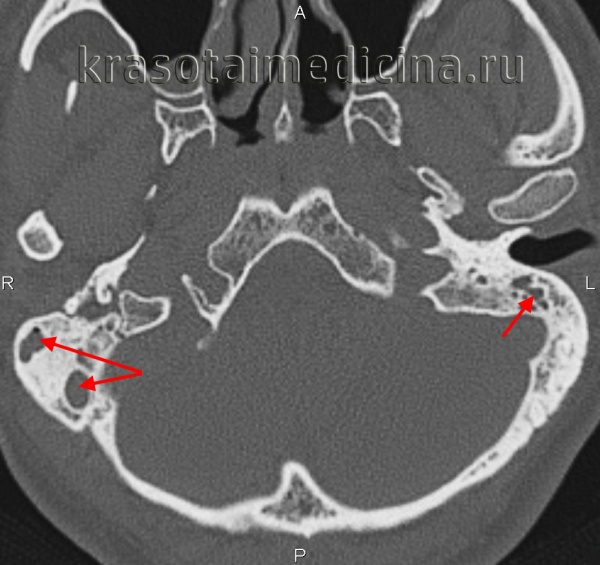

КТ височных костей. Тотальное снижение пневматизации ячеек сосцевидного отростка с обеих сторон. (фото Вишняков В.Н.)

- Рентгенография височной кости. В экссудативной стадии мастоидита обнаруживает завуалированные в результате воспаления ячейки и нечетко различимые перегородки между ними. Рентгенологическая картина пролиферативно-альтеративной стадии мастоидита характеризуется отсутствием ячеистой структуры сосцевидного отростка, вместо которой определяется одна или несколько больших полостей. Лучшая визуализация достигается при проведении КТ черепа в области височной кости.